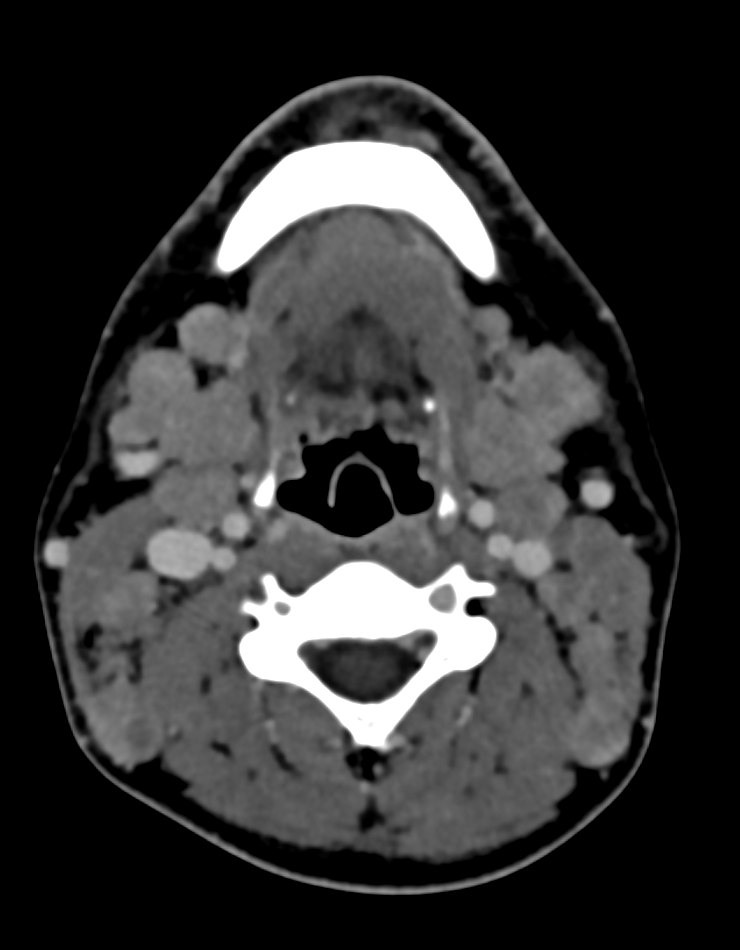

If you're having trouble choosing between an extracellular or hepatobiliary contrast agent for liver MRI, why not both? Read about the indications, protocol, and utility of dual-contrast liver MRI, now available in @RadioGraphics at pubs.rsna.org/doi/10.1148/rg…